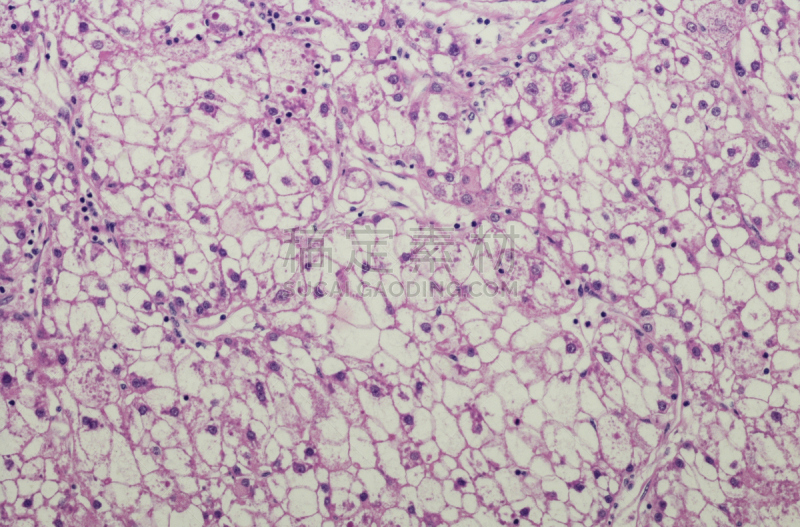

详情

JPG